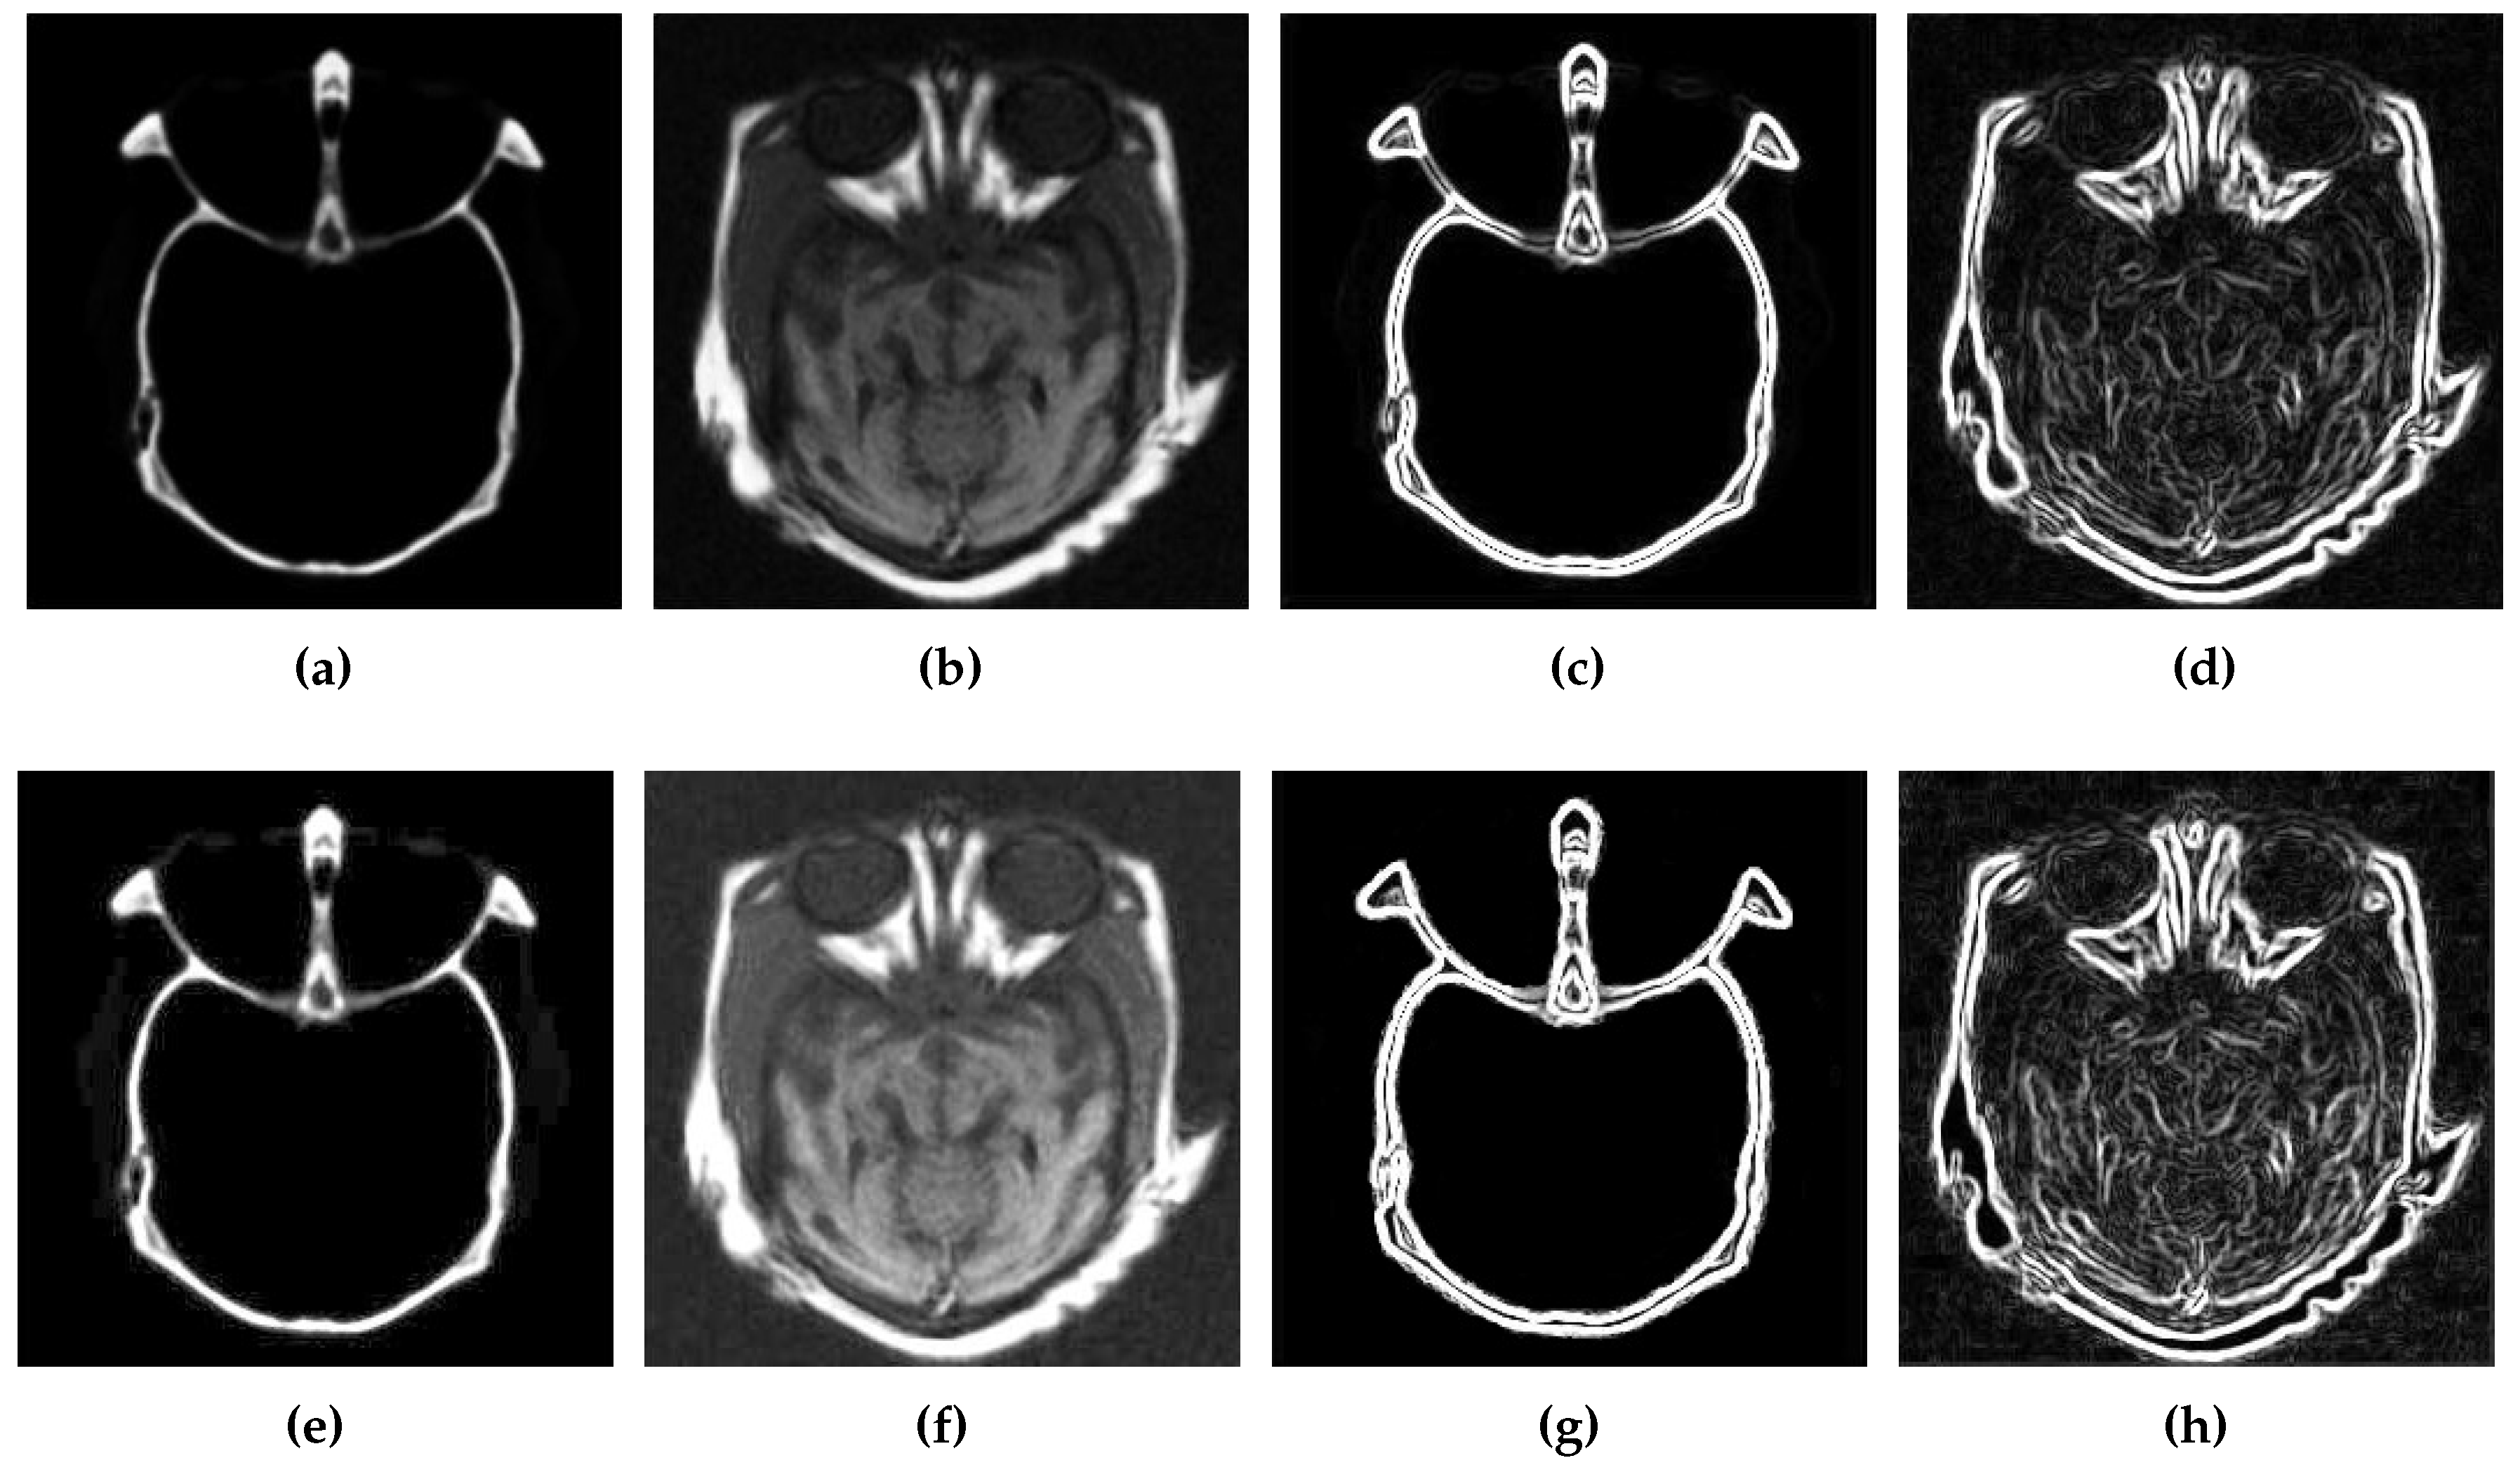

Figure 3 depicts a comparison of edge information in the source and enhanced images obtained after completion of the first two phases of our proposed CSID algorithm. Figure 3a,b present the source CT and MRI images, respectively, while their edge maps are demonstrated in Figure 3c,d, respectively. Furthermore, Figure 3e,f include the improved CT and MRI images obtained after contrast enhancement (as detailed in Section 3.1) and their respective gradient maps are shown in Figure 3g,h. Here, improved edge detection is observed in the image with an enhanced contrast in comparison with edge detection in the original source image. On completion of this phase, CSID proceeds to the third phase, which is discussed in the following subsection.

Figure 3. Edge detection results, where (a,b) are the original source images, (c,d) represent the gradients of (a,b) using the Sobel method, (e,f) shows the images with enhanced contrast using BIMEF, and (g,h) represent the gradients of (e,f) using the Sobel method.